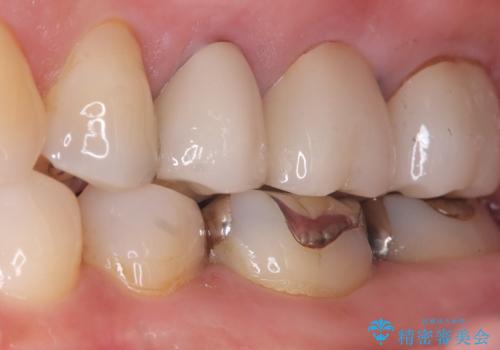

- 主訴:いつも物が詰まる場所があり気になる。衛生士に被せものと土台の境目に汚れが溜まっている箇所があると指摘され気になっている。

過去に入れた被せものと土台の歯との適合が悪く、隙間が出来ておりそこに汚れが溜まりやすい状態になっていました。セラミッククラウンでのやり替えとなりました。

唇側マージン不適なこと説明し、審美性・適合性に優れたセラミッククラウン(スタンダード)でのやり替えとなりました。